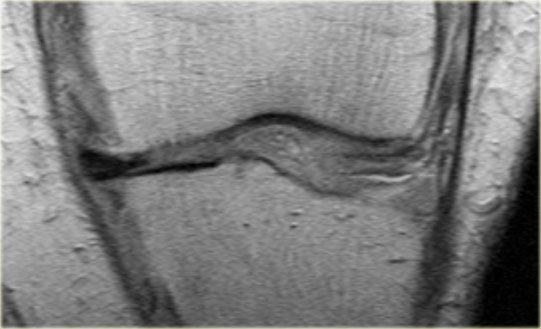

Đây là một trường hợp rách chân sụn chêm trong khác.

Lưu ý rằng sừng sau không còn bám vào xương chày.

Thay vào đó, có thể thấy một khoảng hở (mũi tên cong).

Những tổn thương rách này rất dễ bị bỏ sót khi người đọc nhầm tưởng sừng sau vẫn bình thường.